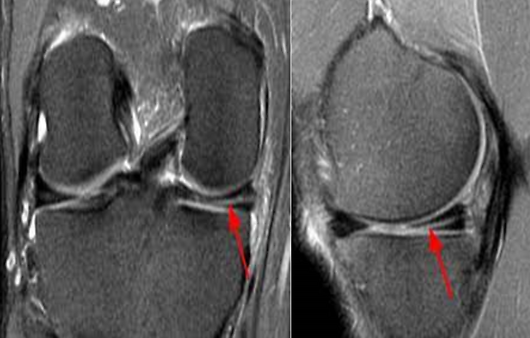

한편 반월상 연골판 파열이 강하게 의심된다면, 반월상 연골판 중 어느 부위가 파열됐는지, 파열된 부위의 크기와 형태는 어떠한지 파악해야 합니다. 이때 활용하는 검사가 MRI 검사입니다. 검사 시간은 오래 걸릴지 몰라도 부상 부위를 정확히 살펴볼 수 있는 방법입니다.